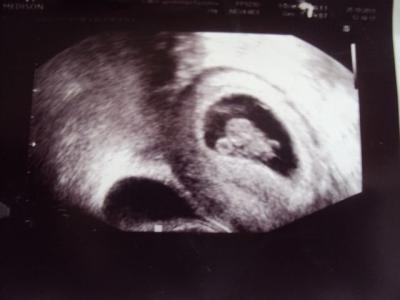

Tady fotka z 8+5 dle UZV, vlevo je vidět ten moč.měch.